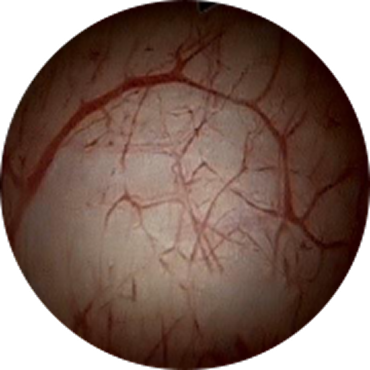

구상화 병변

간질성 방광염

구상화 병변간질성 방광염